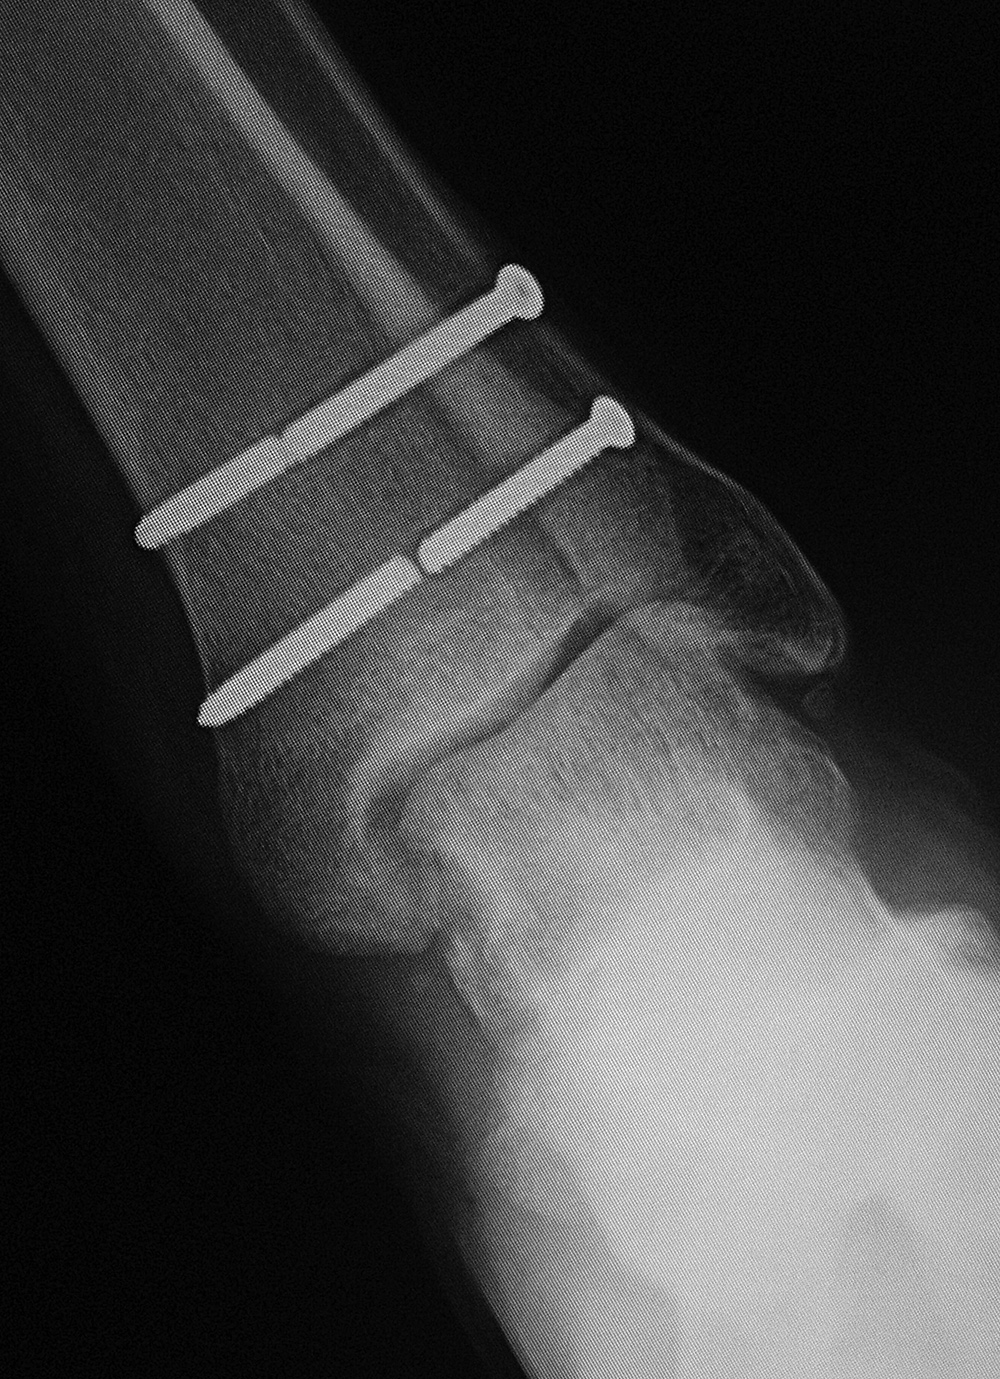

Left first metatarsophalangeal joint arthrodesis screw fractures |

52 year-old man with chronic wound on plantar surface of the left foot and poliomyelitis of the left 2nd metatarsal head (arrow). There is incidental fracturing of two fixation screws from past large toe MTP joint arthrodesis. |